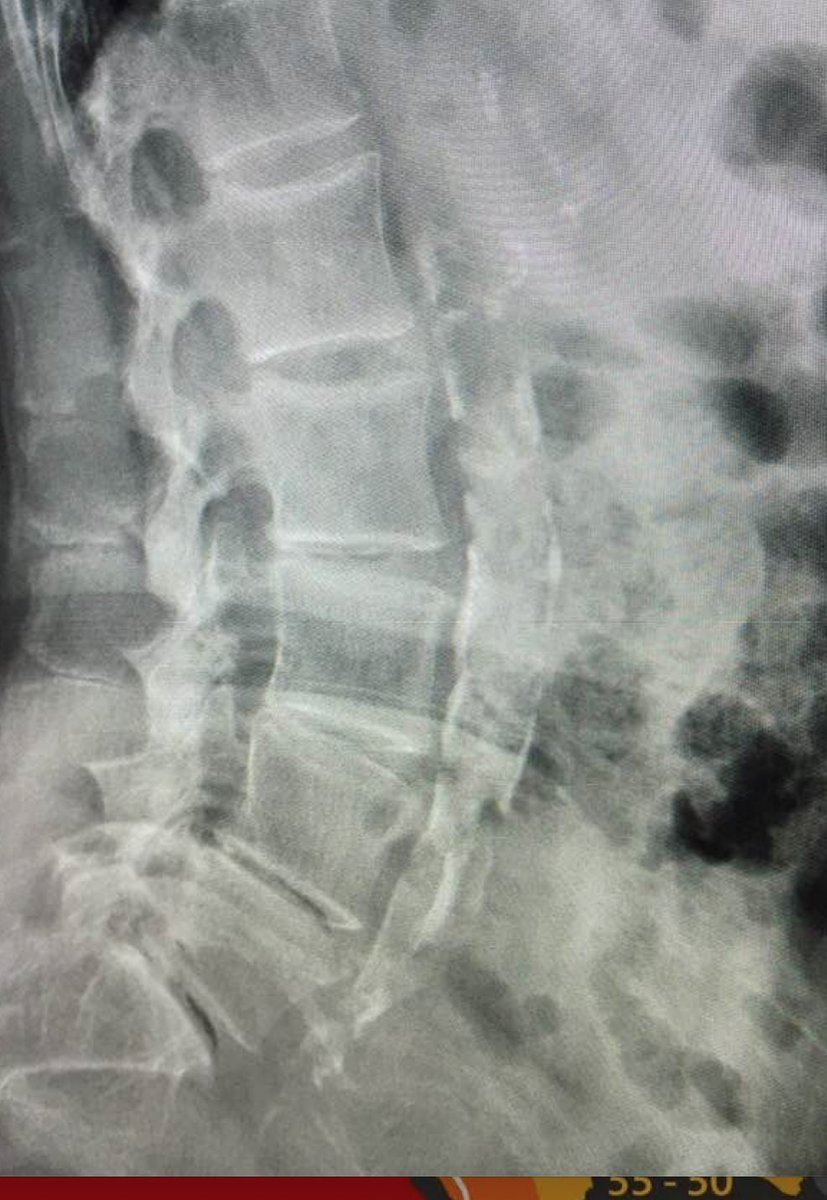

4. Our power grid in the USA oscillates at 60 Hz and the EU works at 50 Hz. Our inner mitochondrial membrane oscillates at 100Hz when cells are using the TCA cycle to burn fats. The power grid is a modulated frequency. This means that the power grid can create an interference pattern in our skin and vessels to change the biochemical programs we can use. 3G-5G has the unique ability to jump conduct to other conductors. Your blood plasma is a magnetohydrodynamic fluid conductor. This means that atherosclerosis in young people who use technology should be expected. This is the aorta in front of the spine of a young tech worker. (below is a 44 yr old hospital IT worker who works in a hospital basement)

The phosphorus ion is critical in this process as a 'qubit' with sunlight in information transfer. In plant PS it is well-known that there is a one-electron redox reaction where free electrons join ADP and Pi to make ATP. No metabolic pathway is needed in this light reaction in plants. In humans, we know the coherent domains in water create millions of free electrons for use in the semiconductive pathways available for cells. These electrons can make ATP in the circulatory system in a similar fashion.

13. The AC frequency in the power grid is modulated so this can be the stimulus to affect a plaque in a peripheral artery to cause blockages and heart attacks. Above, you saw an X-ray of a patient of mine who was an IT worker who was just 44 years old. You can see from the picture right in front of the lumbar spine is a calcified tube running from the heart to the legs which is the aorta. This vessel is not supposed to have any calcium in it at this age. The heteroplasmy levels experienced by this person's aorta show the effect of someone we'd expect in their 80s.